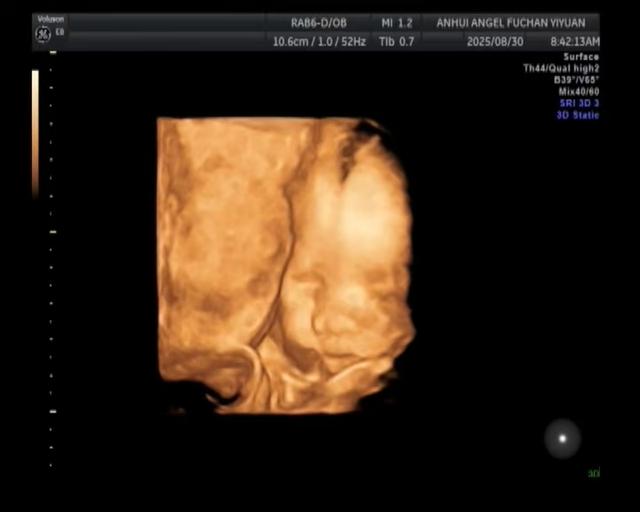

四维怎么刺激胎儿翻身(大排畸秒过攻略)

大排畸顺利通过了[呲牙]下面总结下,四维一次过攻略1.预约时间:最好定在自己胎动频繁的时间点,亲测这能帮你节省不少时间。(我的一般八点多胎动频繁所以约的时间*:8点~10点)2.避免空腹:检查前一定要吃饱,吃饱宝宝才...